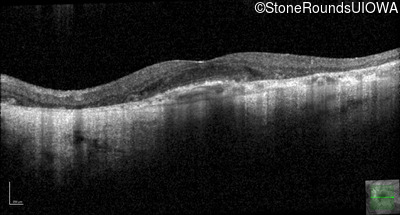

Age at visit: 51 years

This 51 year old woman first experienced some abnormality in her distance vision when she was 27 years old. She feels that her vision has been stable since that time.